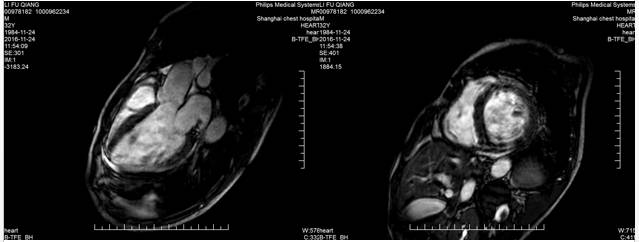

回到我们的病例--心脏MRI

心脏MRI提示

◆2016-11-24心超:

◆左房增大,左室增大;

◆左室壁整体收缩活动度下降,LGE显像提示整个心室壁心肌未见延迟强化现象,故可排除缺血性心肌病

◆LGE显像也未见类似限制性心肌病的特征性心内膜下延迟强化现象。

◆左室内多发条形信号影;LGE扫描未见强化,考虑血栓可能性大。